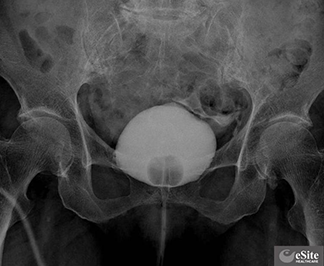

水または生理食塩水が膀胱鏡を通って膀胱を満たします。尿意を感じることがあります。これは正常です。医師はあなたが感じている感情について尋ねます。これは症状の原因を特定するのに役立ちます。

医師が水または生理食塩水で膀胱を膨らませたら、膀胱壁を検査します。この検査では、医師が膀胱鏡の特別なツールを使用して、検査対象の膀胱壁の小さな部分を切除します。若干の締め付け感が生じる場合があります。